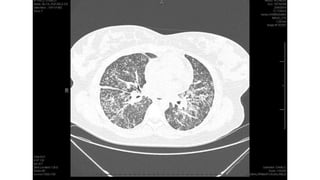

Miliary pattern

Intersticial Randomic micronodular distribution